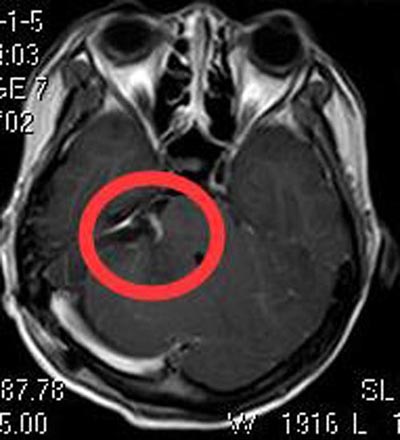

广东三九脑科医院进一步头颅MR检查显示:右侧桥小脑角区占位性病变,大小约4.0cm×3.9cm×2.8cm,脑干及右侧桥臂受压变形。四脑室受压变窄,考虑为听神经鞘瘤。夫妻俩积极地要求手术治疗。完善相关检查后,由综合神经外科鲁明主任主刀,在全麻下经内镜辅助行右侧桥小脑角区听神经瘤切除术,肿瘤呈黄白色,质中,三叉神经、舌咽神经受肿瘤压迫明显,予分块切除,右侧听神经、面神经、三叉神经、舌咽神经均保护完好。术后黄小姐没有出现并发症状。术后病理结果提示:神经鞘瘤。

▲手术后